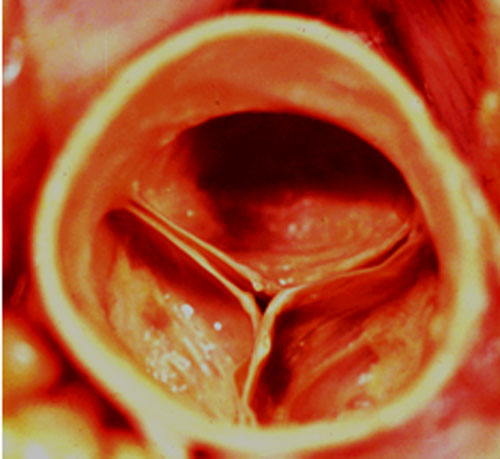

Les orifices artériels, pulmonaire et aortique (figure 2), sont formés chacun d’un anneau fibreux et de 3 valvules dites sigmoïdes.

Il existe 2 appareils valvulaires auriculo-ventriculaires (figure 3) formés d’un anneau fibreux et d’un système valvulaire constitué de valvules, de cordages et de piliers. L’orifice tricuspidien a 3 valvules (Antérieure = A, Septale =S, Postérieure =P), le mitral n’en a que 2, (grande et petite valves) chacune étant divisée en 3 segments (A1,A2,A3 et P1,P2,P3).